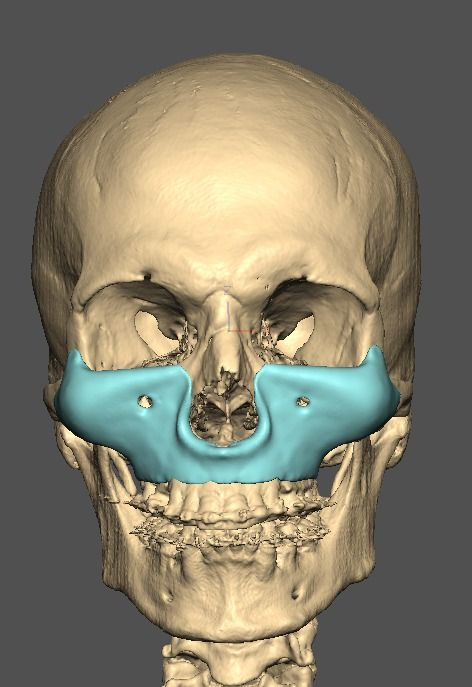

A lot changed since the initial design

current

It's going to be split into either 5 or 7 pieces.

current

It's going to be split into either 5 or 7 pieces.